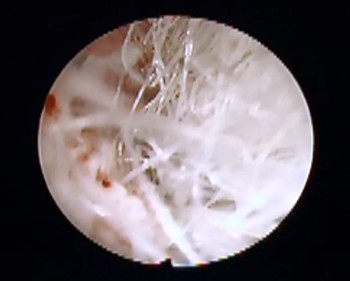

术后10天、15天检查

术后再次行宫腔镜下阴道内镜检查发现阴道中段封堵性粘连,镜下分离粘连后,阴道基本恢复正常,采取防止粘连措施,嘱咐小馨妈妈10天后再行复查。复查时宫腔镜下见小患者阴道形态恢复正常,各壁创面基本恢复正常。